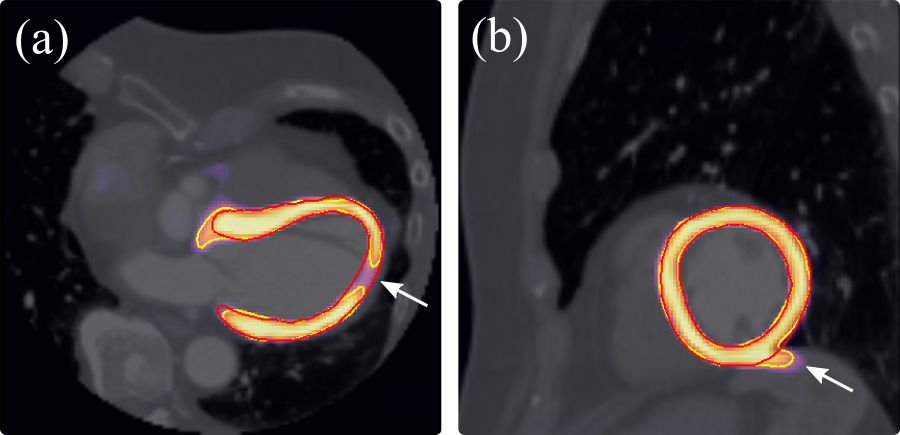

Models were initially trained with no data augmentation, and a significant drop in performance was observed from the ITN to 1-pass DSC (Table 1, left). This highlighted the importance of incorporating spatial augmentations when training the Atlas-ISTN with a limited dataset. The ITN learns both global and local image features, and can primarily rely on local image features to make accurate voxel-wise predictions. The STN performance however depends more heavily on learning global image features, given that the predicted displacement field must operate across the entire image to transform SoI to significantly different orientations, scales and morphological configurations. The bottom two rows of Figure 10 show the outputs of Atlas-ISTN on particularly challenging cases, where significant global and local deformations are required to register the undeformed atlas to the target SoI. The ITN and 1-pass results are inadequate, while the refinement suitably fits the atlas labelmap to the target SoI.

Table 1 shows the results of the U-net and Atlas-ISTN using the high quality 19 case LSA test set, for which labels of all chambers were available. For models trained with no data augmentation, we observe slight improvements of the ITN over the U-net for LVM, LV and RV DSC (, and , respectively), but not for other structures. The 1-pass performance of Atlas-ISTN falls short of the ITN across all metrics for the aforementioned reasons. Refinement produces the best results across almost all metrics, and although DSC improves by a moderate over the ITN, performance on ASD and HD metrics improves significantly. U-net1cc also improves over the U-net in terms of HD and to a lesser extent ASD, but is almost always out-performed by refinement. Fig. 11 shows examples where U-net1cc is unable to correct certain false positive and false negative predictions, while refinement of Atlas-ISTN does.